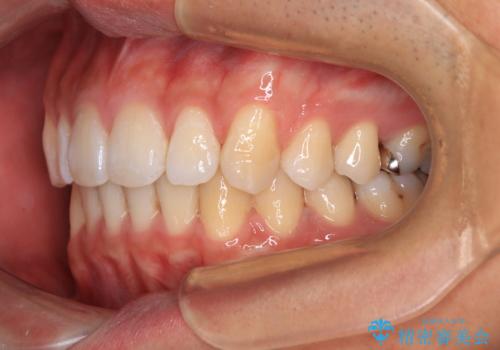

深い咬み合わせと前歯の隙間 ハーフリンガルによる矯正治療

- 咬み合わせにより上顎正中に隙間ができているとのことで来院された患者様です。

矯正治療中に結婚式があったそうですが、隙間も改善しており、一部装置を外すことなく挙式できたとのことでした。